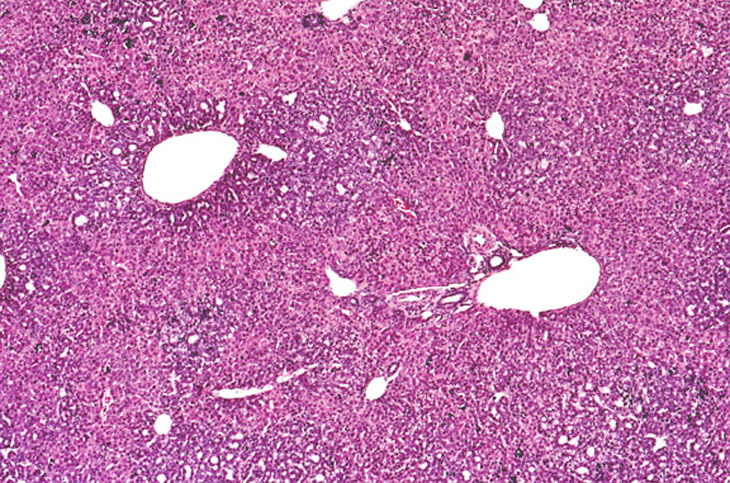

Ductular formation of hepatocytes in this 2-week old AL-TAg x AL-myc mouse has a predominantly centrilobular localization.

An altered hepatocyte focus is arising in an area of ductular formation in this 2-week old AL-TAg x AL-myc mouse.